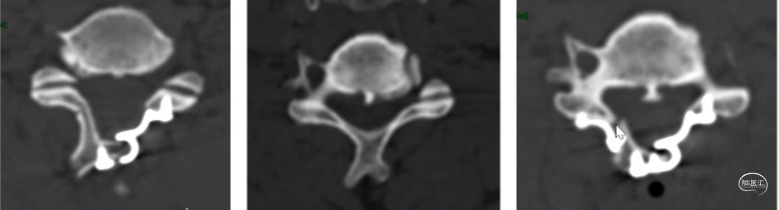

后路单开门:门轴断裂